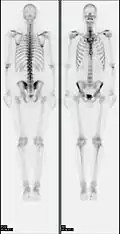

- 2D: Сцинтиграфия (от лат. «знать») — это использование внутренних радионуклидов для создания двухмерных изображений.

Сканирование костей всего тела с помощью ядерной медицины. Сканирование костей всего тела в ядерной медицине обычно используется для оценки различных патологий, связанных с костями, таких как боли в костях, стрессовые переломы, доброкачественные поражения костей, инфекции костей или распространение рака на кость.